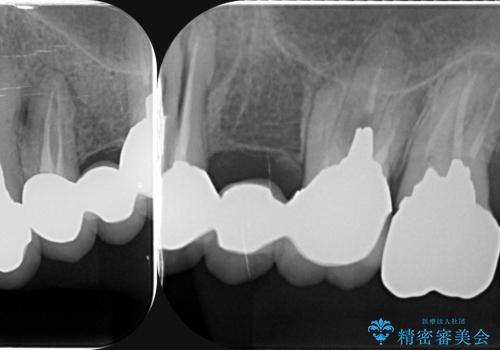

虫歯による歯の喪失 インプラントによる咬合機能回復

- 深い虫歯や歯の破折、多数の問題を口腔内に抱えて来院されました。

虫歯の徹底的な除去、安定した噛み合わせを達成するインプラント治療、深い虫歯、根管治療といった複数の治療項目を一つづつ積み重ね、長期的な予後を目指します。